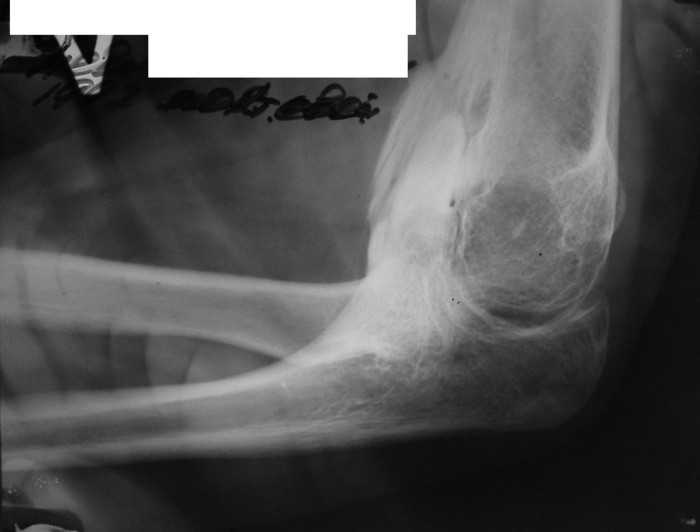

Re: Врожденная аномалия, множественные экзостозы

рентгенограммы